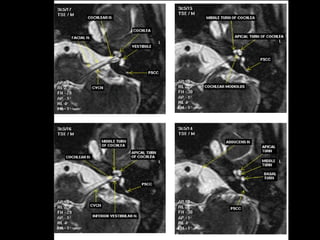

T2

 The images are shown from a left temporal bone,

from

 cranially to caudally. All images have a 0.7 mm

slice

 thickness.

IAC MRI Anatomy and Search Pattern :

3D CISS sequence (thin axial high T2 sequences)

Review axial images superior to inferior

Look at CN V and Meckel’s cave Look at Petrous Apex

Look at the Cerebellopontine angle Look at the IAC and evaluate it’s origin

Notice CN 7 & 8 in the IAC and

their close relationship to AICA

More inferiorly, evaluate the cochlear

and vestibular nerves

Finally:

Evaluate the following fluid filled

structures that are T2 bright:

•Semicircular canals

•Vestibule

•Ovoid in shape

•Cochlea

•Modiolus: hypointense area

at base